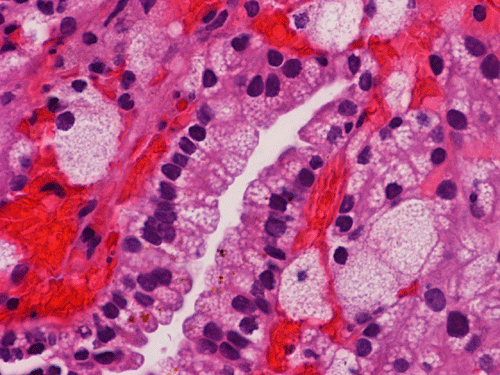

On FNA with Pap stain, clusters of cells with a papillary structure are present (Panel A). A delicate fibrovascular core can be seen at the center (arrow in Panel B). In higher magnification, two population of cells are present. While one of the population appears as solid sheets of polygonal epithelial cells with increased nuclear cytoplasmic ratio and distinct cell border (arrow head in Panel C), there are also many cells with distinctly foamy cytoplasm, lower nuclear cytoplasmic ratio and bland nuclei, and indistinct cell border (arrow head in Panel C). The foamy cells are most consistent with foamy macrophages. A distinct nucleoli is present in the epithelial cells (Panel D). The papillary morphology is well demonstrated in the cell block (Panel E, F, and G). Characteristically, the papillary structures are formed by a central core of foamy macrophages and covered by a epithelial cells. The epithelial cells but not the foamy macrophages are immunoreactive for CD10, AMACR, and CK7 (Panel H, I, and J).

Histologically, the proportion of papillary growth can vary. While papillary growth can be the dominant pattern in some tumor, tumors composed of predominantly solid growth areas can be seen. The papillary growth has fine, delicate fibrovascular cores. Foamy macrophages are usually abundant and they are usually wonderful diagnostic suggestions. However, it should be noticed that areas that lack foamy macrophages can occur. This is particularly important when the specimen is small such as FNA specimens. The tumor cells fall into two major cytologic types. Type 1 tumors cells vary from small cells with inconspicuous pale cytoplasm and small, uniform, spherical nuclei with small or invisible nucleoli. Type 2 tumor cells are larger cells with abundant eosinophilic cytoplasm and large, spherical nuclei, prominent nucleoli and pseudostratified arrangement. Mixed pattern within the same tumor is not uncommon. 1, 2, 4, 5